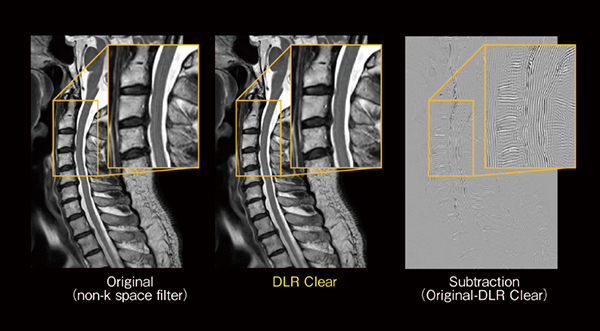

今回,新たに搭載した「DLR Clear」は,AI技術を活用した画質向上技術であり,MRIの撮像原理上発生するトランケーションアーチファクトの低減や画像先鋭度を向上することが期待できます。図6に頸椎のT2強調画像の矢状断を示していますが,DLR Clearを付加することにより,しま状のトランケーションアーチファクトが低減していることがわかります。また,図7に肝臓のT1強調画像を示していますが,同じピクセルサイズで撮像しているにもかかわらず,DLR Clearの画像先鋭度が向上していることがわかります。このDLR Clearは,FSEやDWIなどの2Dシーケンスのみならず,RADAR(RADial Acquisition Regime)のようなradial scanや3Dシーケンスにも幅広く適応することが可能であり,MRIの画質向上が期待できる機能です。

図6 DLR Clearによるトランケーションアーチファクト低減効果

頸椎のT2強調矢状断画像。DLR Clearを付加することにより,しま状のトランケーションアーチファクトが低減していることがわかる。OriginalとDLR Clearの差分画像ではしま状のアーチファクトが確認でき,DLR Clearによりトランケーションアーチファクト部分の信号が低減していることを示す。